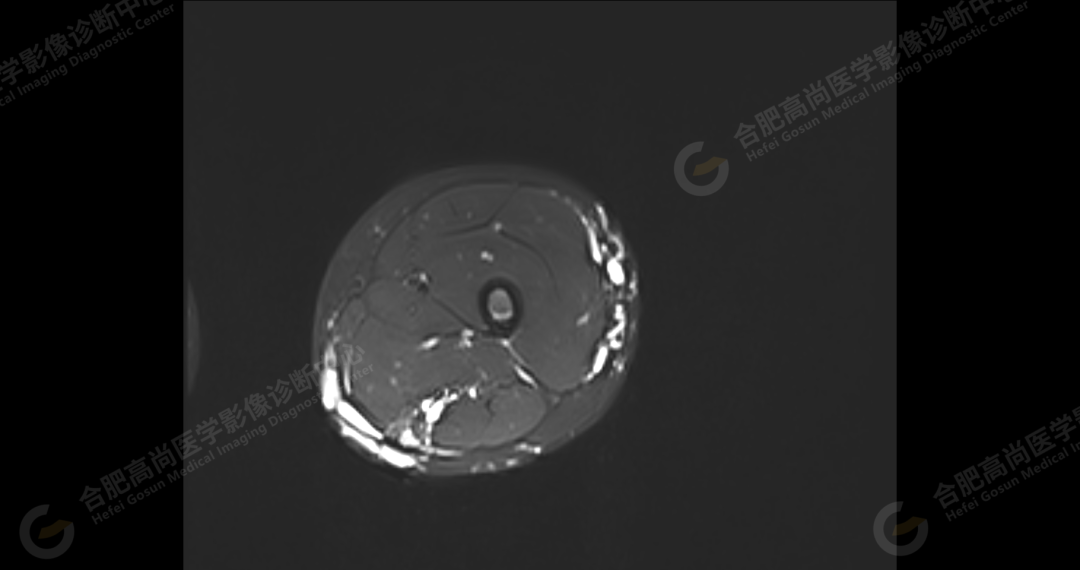

影像表现

左侧髂骨内侧及闭孔内肌前方可见网格状异常信号影,边界欠清,T1WI 呈低信号,T2 压脂呈高信号,病变连续,延伸至臀肌内;左侧臀肌间隙及皮下、左大腿后部肌肉群及皮下、左膝前外侧及腘窝皮下、左小腿后侧皮下累及比目鱼肌及内外侧腓肠肌、左内外踝皮下、左足背足底及左足肌间隙内可见大片状、结节状弥漫性异常信号影,形态不规则,分布不均匀,边界不清,T1WI 呈低信号,T2WI 压脂后病灶呈高信号,部分病灶内可见网格状低信号,左足部肌间隙增宽,第 2-4 跖骨稍受压,骨质结构完整。左髋关节、膝、左踝关节间隙正常,无明显狭窄及增宽,关节面光滑,关节腔内无积液,左股骨、胫腓骨及踝部各组成骨骨质结构完整,未见明显异常改变。